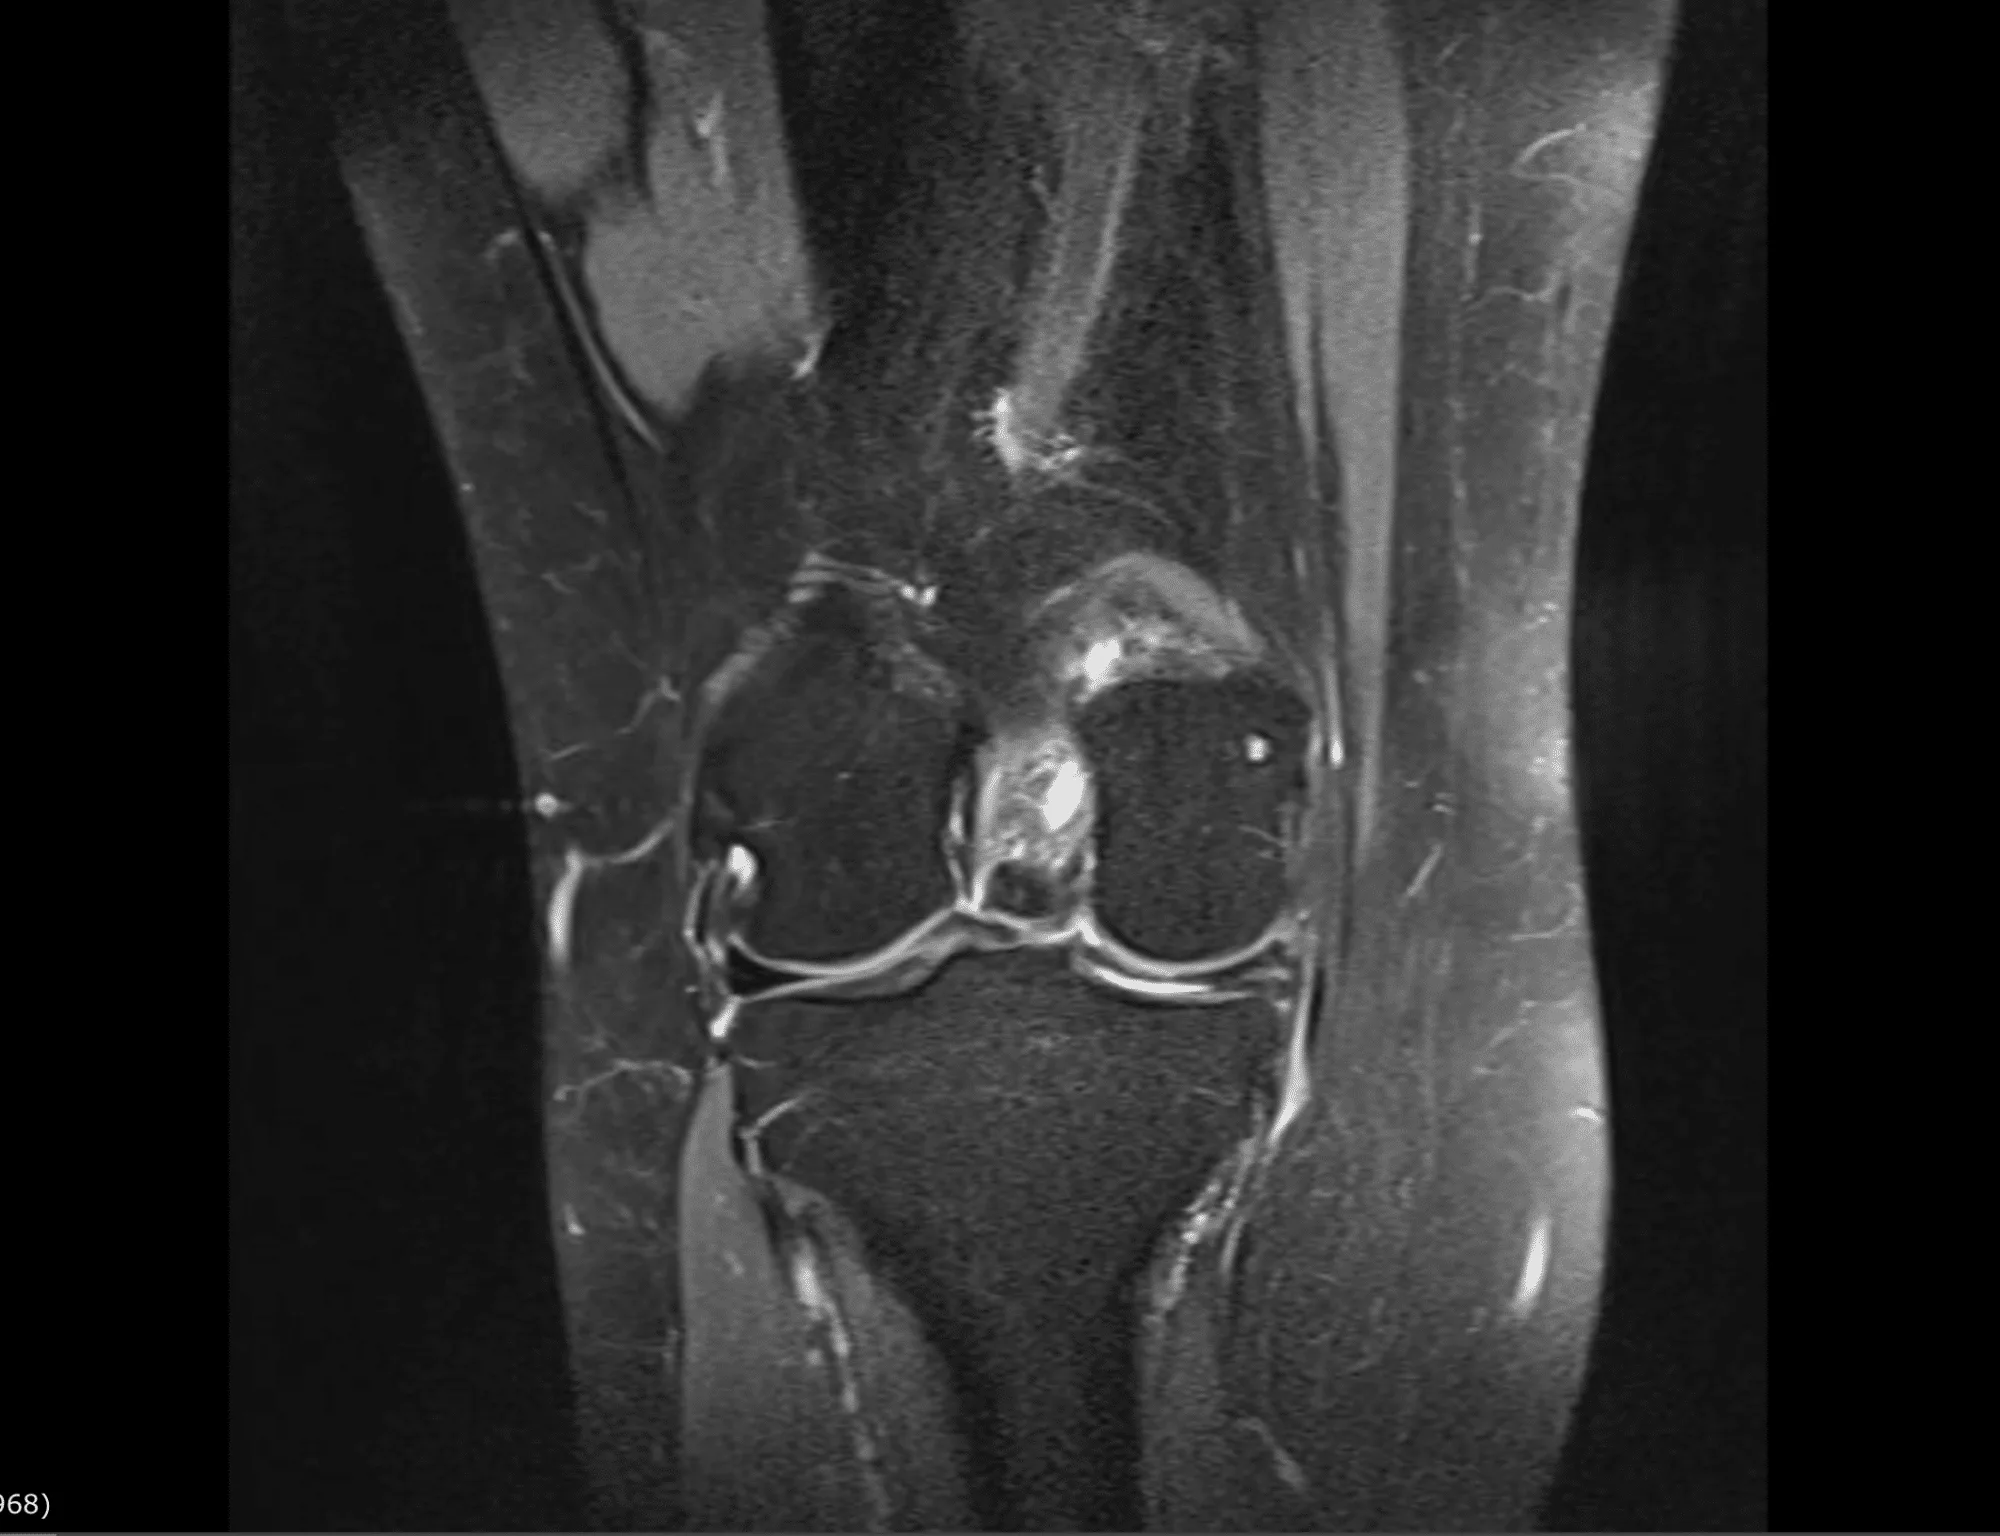

Der Gelenkknorpel ist die Gleitschicht in den Gelenken, die den Knochen im Gelenk aufliegt. Das Knorpelgewebe ist nicht durchblutet und wird über die Gelenkflüssigkeit ernährt. Unfälle oder zunehmender Verschleiß können zu Verletzungen oder einer Ausdünnung der Knorpelschicht führen. Aufgrund der fehlenden Blutversorgung heilen Knorpelschäden nicht von alleine. Umschriebene Knorpeldefekte können entweder ohne Operation (konservativ) oder durch verschiedene moderne, häufig minimalinvasive Operationsmethoden saniert werden. Zur Diagnosestellung und Therapieplanung erfolgt bei uns eine ausführlicher Untersuchung und Beurteilung Ihrer MRT-Bilder.